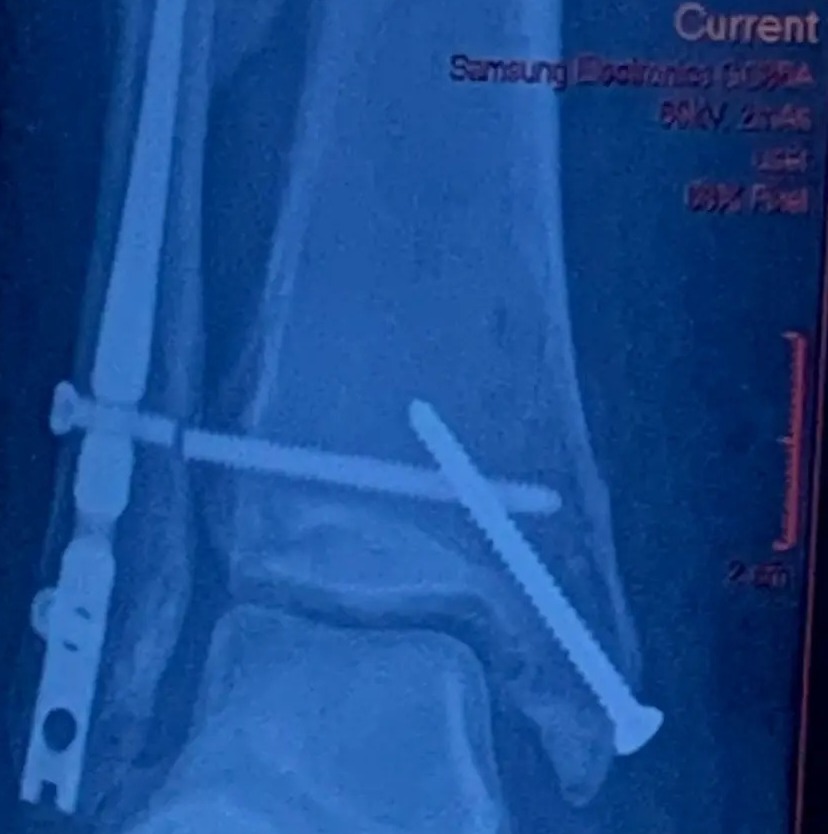

وتسبب الكلب الصغير في إصابة الفتاة بتمزق في أربطة القدم، وكسر كاحلها، حيث أخبرها الطبيب بأنها سوف تصاب بالتهاب في المفاصل، وذلك خلال الـ 4 سنوات المقبلة.

كما اندهش الأطباء عندما علموا أن تلك الإصابات ناجمة بسبب كلبًا صغيرًا، وقالوا إن عادًة تلك الإصابات نراها في حالات اصطدام لاعبي كرة القدم في المباريات.